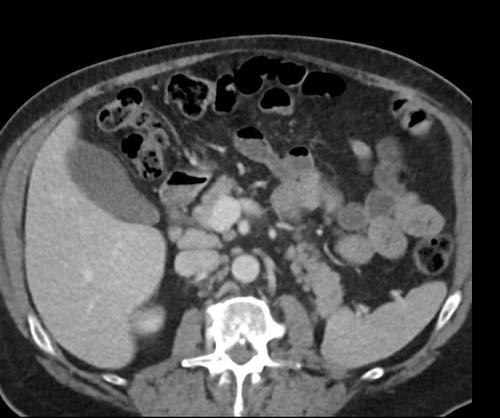

Ca lâm sàng 2

Cuộn qua các lát cắt.

Bạn có thể phát hiện tất cả các tổn thương cấy ghép phúc mạc không?

.jpeg)